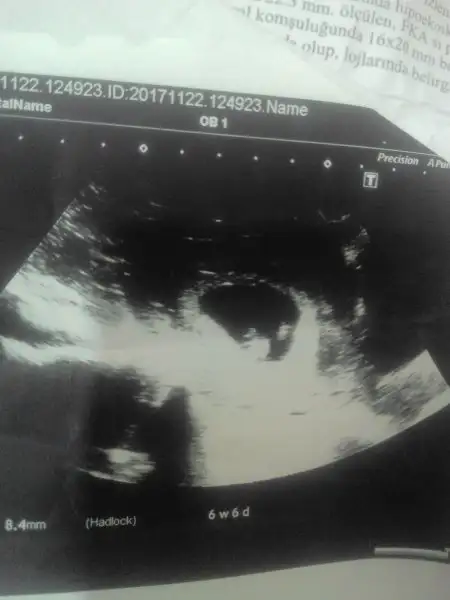

Bebeğin plasentası solda parlıyor ilk resimde. Kız derler ama. Dr ne dedi sana?evet canim bak atiyim tekrar 0Eki Görüntüle 2089138 asagidakide 8.6Eki Görüntüle 2089140